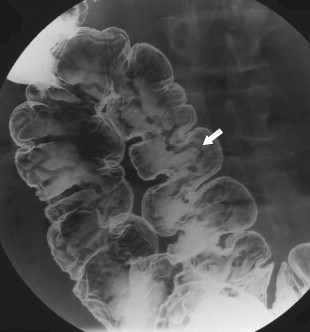

Ultrasound (US) sometimes shows a hypoechoic cystic mass with a thick wall, which has an echogenic outer layer and hypoechoic inner layer. On BE the cyst produces a mass effect of adjacent bowel and on CT appears as a nonenhancing mass, compressing or displacing the adjacent bowel, which may contain simple fluid, hemorrhage, or proteinaceous fluid ( Fig. 5-4 ). On MRI the enteric cysts are usually hyperintense on T2-weighted imaging, reflecting their cystic nature ( Fig. 5-5 ). Because many duplication cysts contain ectopic gastric mucosa, a Tc-99m pertechnetate radionuclide study can often show radionuclide uptake, which can also be observed within a Meckel diverticulum for the same reason.

Figure 5-4, Axial contrast-enhanced CT in a 46-year-old woman with a 4.5-cm homogeneous pararectal mass ( arrow ) caused by rectal enteric duplication.

Figure 5-5, Axial ( A ) and sagittal ( B ) T2-weighted imaging in a 30-year-old woman with a cystic 4.5-cm mass ( arrows ) in a posterolateral perirectal location resulting from a rectal duplication cyst.